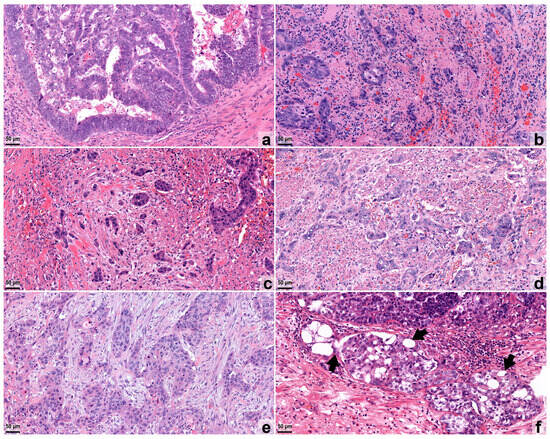

2.2. Histological Work-Up and Assessment